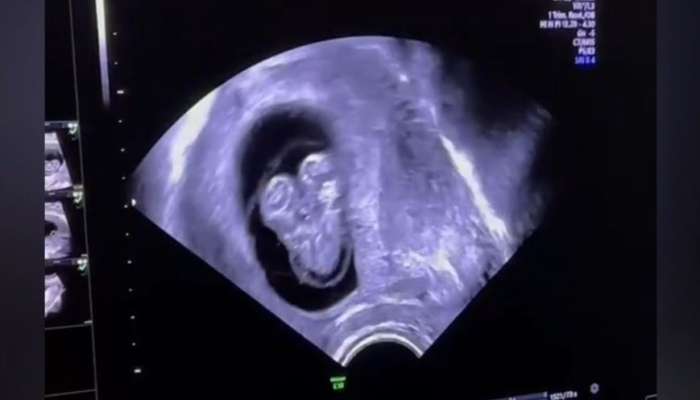

Həkimlər